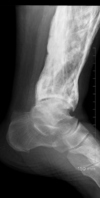

Bico talar

Coalizão calcaneonavicular.